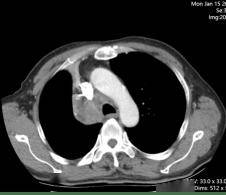

所谓的精准武器,就是当时国内新获批的可医保报销的高选择性MET抑制剂。1月12日,69岁的老李开始口服这种靶向药物——MET抑制剂。仅仅28天,咳嗽、痰血和喘憋就明显减轻。复查CT,原本被肿瘤压瘪的右上肺重新张开,连支气管镜下的“菜花”样新生物也缩小了近一半。老李高兴地说:“睡觉不再被憋醒,走路也能跟上儿子了。”

靶向治疗前

靶向治疗1个月后

化疗+免疫治疗前

化疗+免疫治疗2周期后

从2024年1月的“痰中带血”到2026年新年的“全家团圆”,老李的治疗轨迹像一张清晰的路线图:精准检测→靶向先锋→局部放疗→化免联合。每一步,都离不开北京胸科医院肿瘤中心一病区团队的判断与调整;每一次转危为安,也让更多患者和家属看到:晚期肺癌,依然可以长期、高质量地带瘤生存。